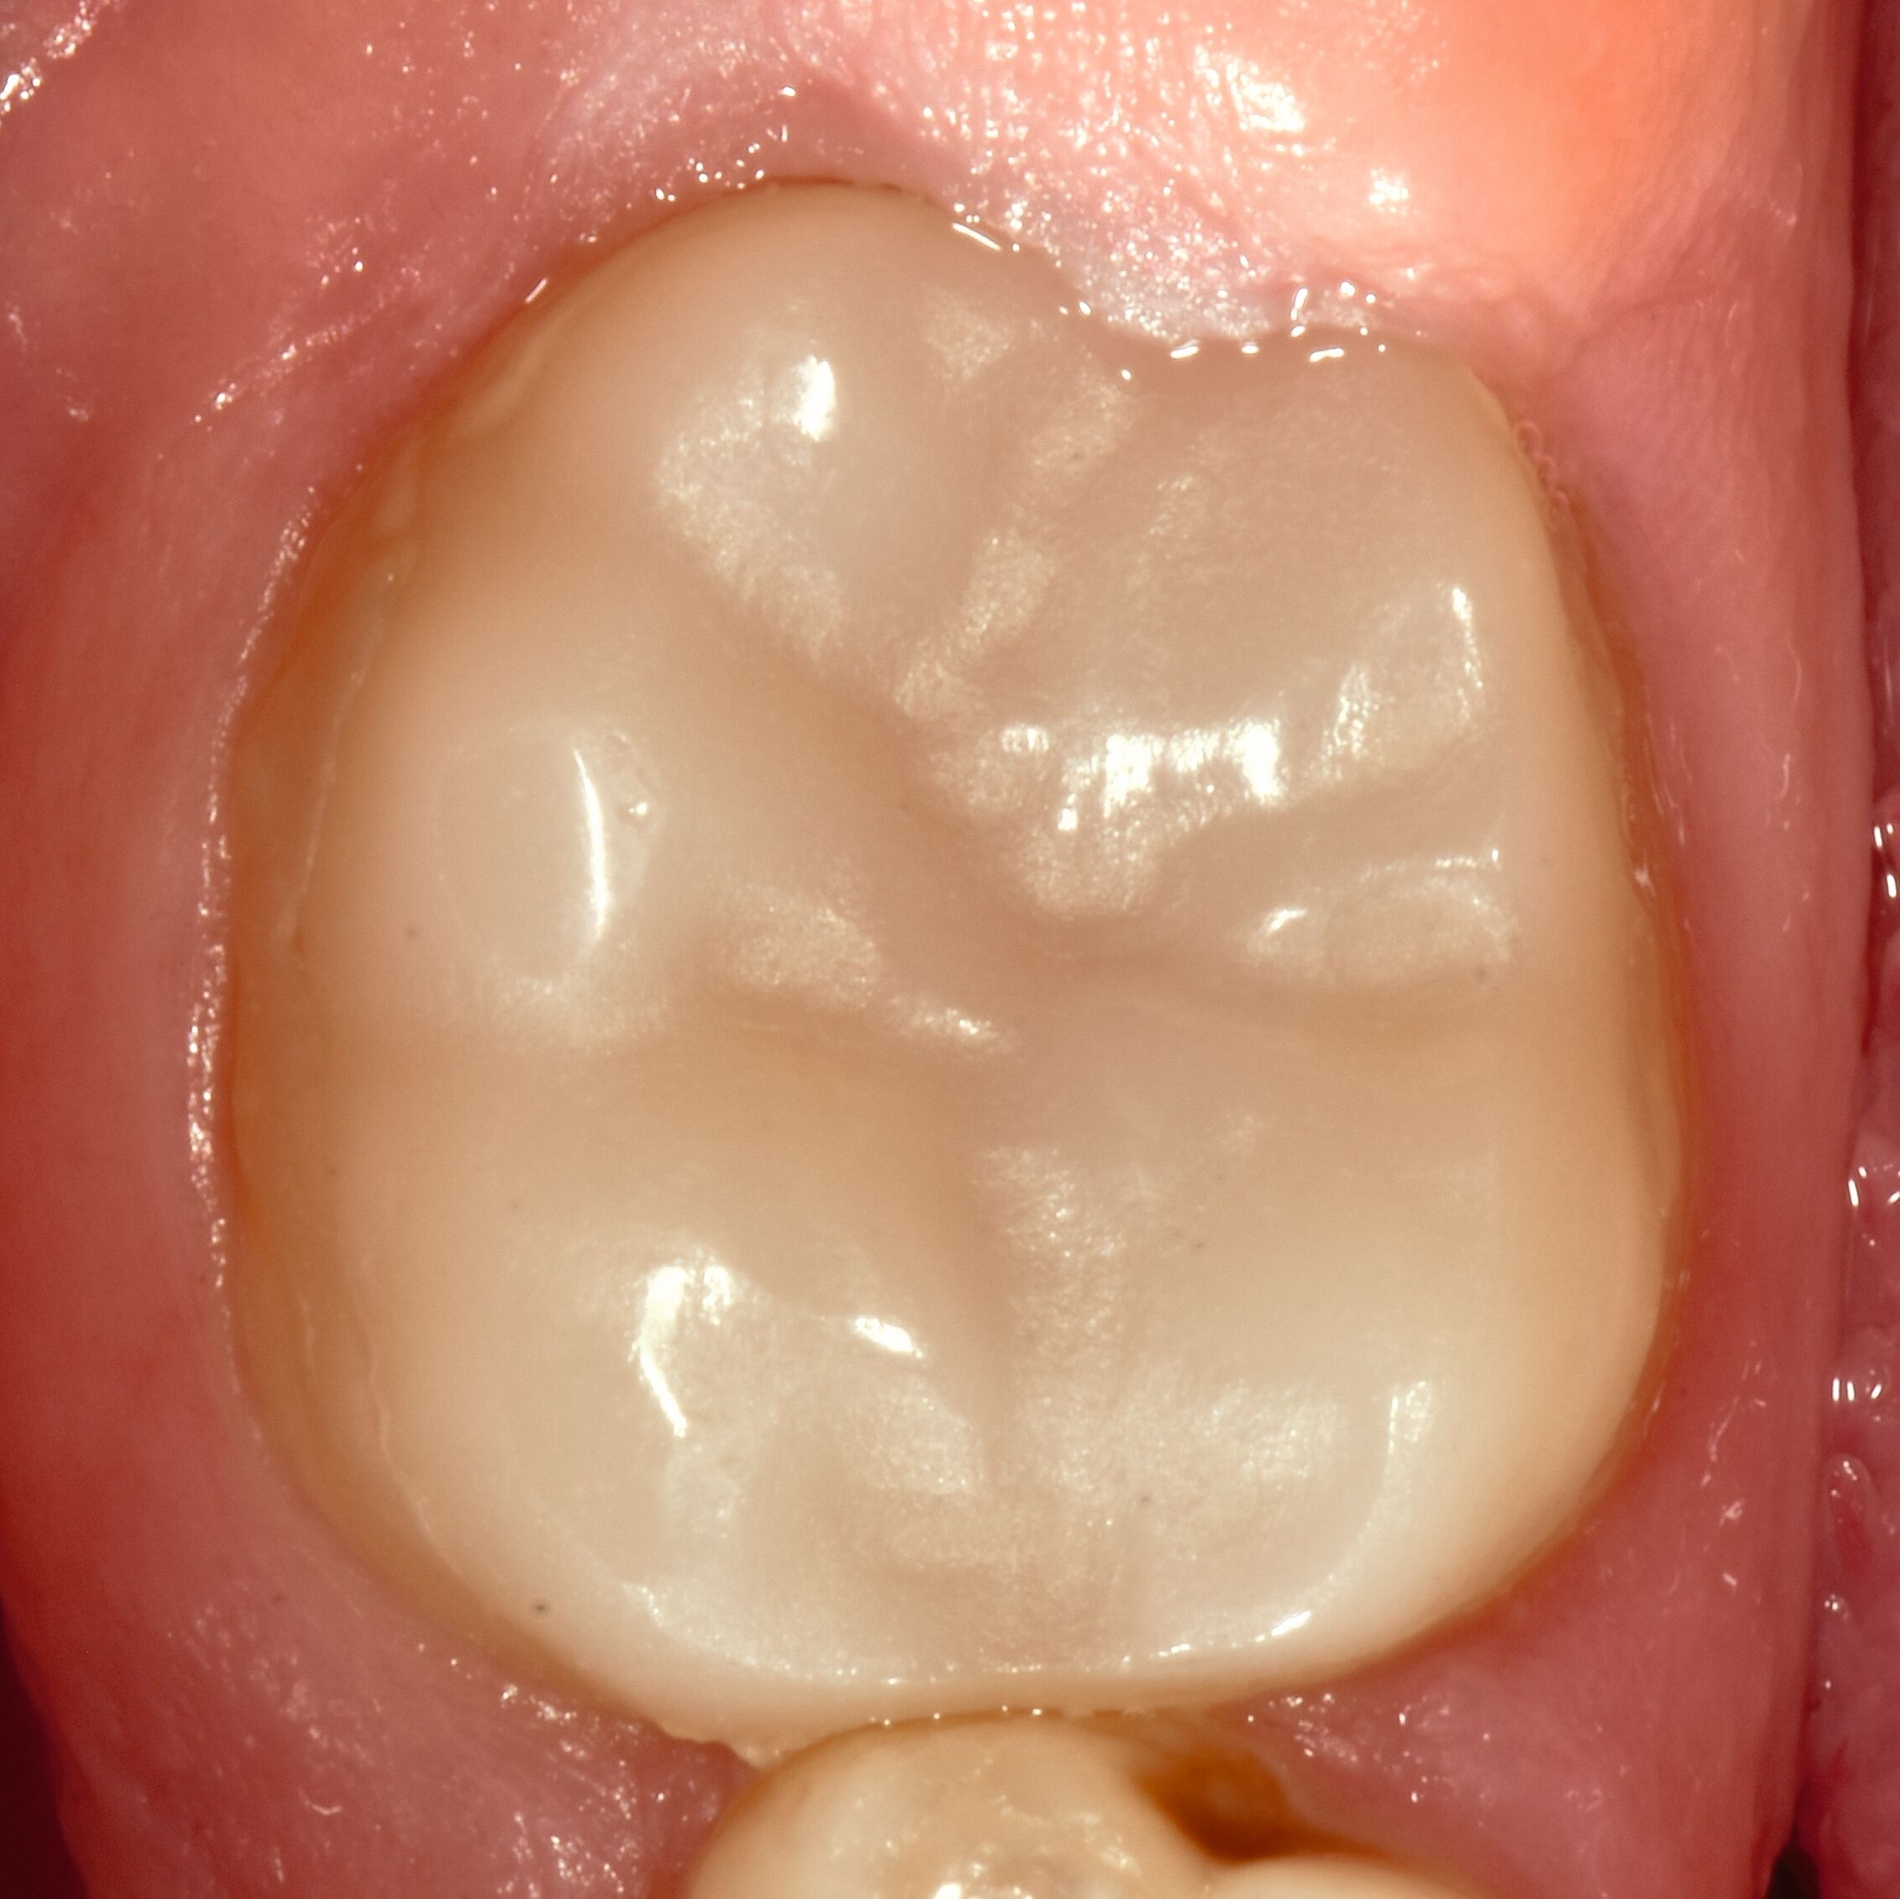

Das klinische Erscheinungsbild an bleibenden Zähnen zeigt typischerweise weißlich-gelbe bis gelblich-braune Opazitäten, die zumindest in einigen Bereichen durch eine scharfe Abgrenzung (engl.:„demarcated opacities“) zum gesunden Zahnschmelz charakterisiert sind (Abbildungen 3 und 4). Die abgegrenzten Hypomineralisationen befinden sich mehrheitlich im Bereich der inzisalen Kronenhälfte unabhängig von dem Auftreten an Front- oder Seitenzähnen. Die Ausprägung am Zahn kann dabei auf einzelne Areale oder Höcker begrenzt sein.

Für die Dokumentation und Klassifikation der MIH wurden verschiedene Systeme vorgeschlagen. Als historisch und veraltet gilt der (modifizierte) DDE-Index. Demgegenüber haben die Kriterien der EAPD – abgegrenzte Opazitäten (Abbildung 3 und 4), Schmelzeinbrüche (Abbildung 5), atypische Restaurationen (Abbildung 6) – mittlerweile die weiteste Verbreitung gefunden. Diese wurden 2003 erstmals zur Beschreibung der MIH auf empirischer Basis publiziert [Weerheijm et al., 2003] und den Jahren 2010 und 2022 im Rahmen der damaligen MIH-Workshops bestätigt [Lygidakis et al., 2010; 2022].